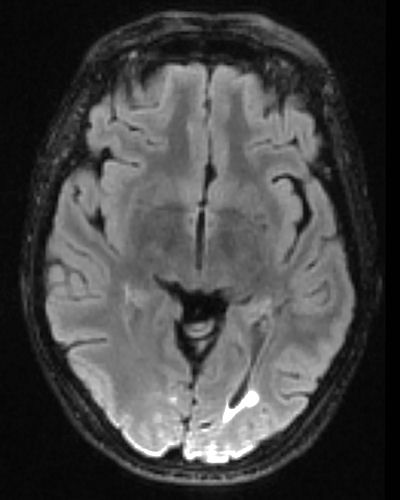

Mark the lesion in the scan